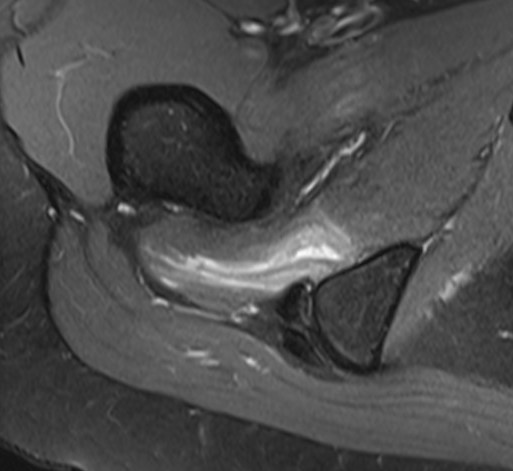

MRI

Reduced ischiofemoral space - distance between the lesser trochanter and the ischial tuberosity

Reduced quadratus femoris space - distance between hamstring tendon and iliopsoas

Inflammation / edema in quadratus femoris +/- fatty degeneration

Singer et al Skeletal Radiol 2015

- systematic review of 190 hip MRI of patients with ischiofemoral impingement

- compared to controls

- ischiofemoral space < 15 mm: sensitivity  77%, specificity 81%, accuracy 78%

- ischiofemoral space < 10 mm: sensitivity 79%, specificity 74%, accuracy 77%.